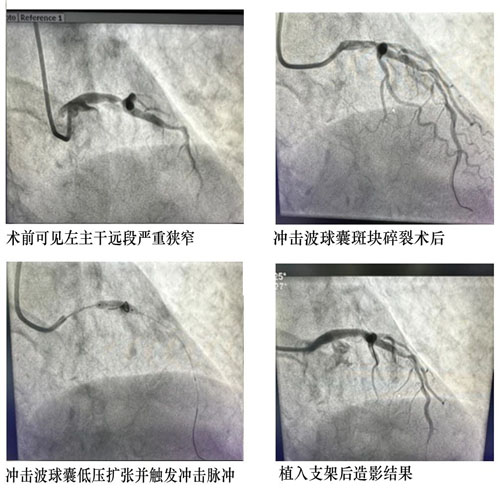

近日,我院心血管內(nèi)科獨(dú)立完成本地區(qū)首例冠脈血管內(nèi)沖擊波球囊斑塊碎裂術(shù)。

患者,男,80歲,1個(gè)月前因胸痛收住院。冠脈造影提示左主干至前降支鈣化病變導(dǎo)致80-90%狹窄,右冠脈閉塞。患者冠脈病變嚴(yán)重,手術(shù)風(fēng)險(xiǎn)較高,先期開通閉塞右冠病變并植入支架治療,此次處理左主干病變。

患者年齡大,左主干重度狹窄并嚴(yán)重鈣化,常規(guī)PTCA(經(jīng)皮冠狀動(dòng)脈腔內(nèi)血管成形術(shù))難以充分處理病變,可能導(dǎo)致支架無(wú)法順利通過(guò)、膨脹不全等風(fēng)險(xiǎn)。心血管內(nèi)科CCU討論后決定應(yīng)用沖擊波球囊,選擇3.5×12mm Shockwave球囊精確定位于LM-LAD鈣化病變嚴(yán)重處,根據(jù)標(biāo)準(zhǔn)操作流程,4ATM低壓力擴(kuò)張球囊,累計(jì)觸發(fā)2個(gè)周期的沖擊波鈣化斑塊碎裂術(shù),利用聲波壓力震碎血管壁內(nèi)鈣化沉積,解決了嚴(yán)重鈣化病變普通球囊無(wú)法充分?jǐn)U張的難題,復(fù)查冠脈造影見鈣化病變狹窄明顯減輕。經(jīng)1小時(shí)手術(shù)治療,成功植入藥物支架1枚,解除血管狹窄,患者未再有癥狀,順利出院。